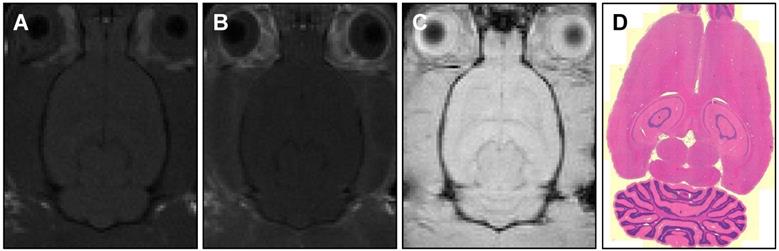

Figure 7

MR images of (A) pre-treatment (T1-weighted) and (B, C) post-treatment (T1-weighted, T2*-weighted) axial slices showing no detectable BBB-opening or damage. Histology sections (D) with H&E staining and 5 μm slice thickness also confirm no tissue damage.

Tissue assessment

Contrast-enhanced MR imaging showed no detectable BBB disruption or damage post-treatment (Figure 7A-C). Histological slides with H&E stain showed no observable red blood cell extravasation or detectable edema (Figure 7D, 7E). There were no signs of toxicity or necrosis in the gross histology or the H&E stained sections of kidney or liver (Figure 8). Histology also appeared normal in the heart, lung and spleen samples (Figure 8), suggesting systemic delivery of pentobarbital-loaded nanodroplets was well tolerated after 2 hours. For long term assessment, animals assessed for behavioral changes were monitored for multiple weeks following treatment and showed full recovery in motor ability and no signs of toxicity.